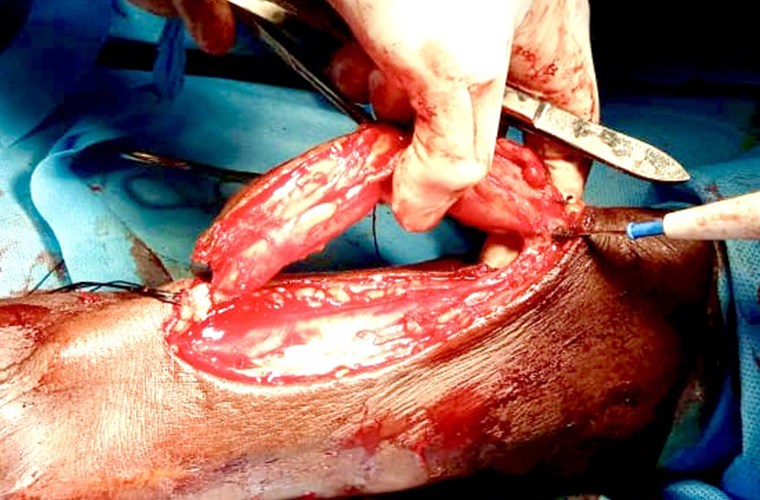

Dr.DineshShanmugaSundaram is specialized himself in each & every part of Cardiovascular & Thoracic Surgery both in Adult & Paediatric or Congenital Heart Diseases. He is both an ethical & academic surgeon,changed the trend in Cardiac Surgery to fast & safe level, as prolonged procedures in Cardiac Surgery increases postoperative complications. We aim at decreasing perioperative complications to the maximal level. Read More